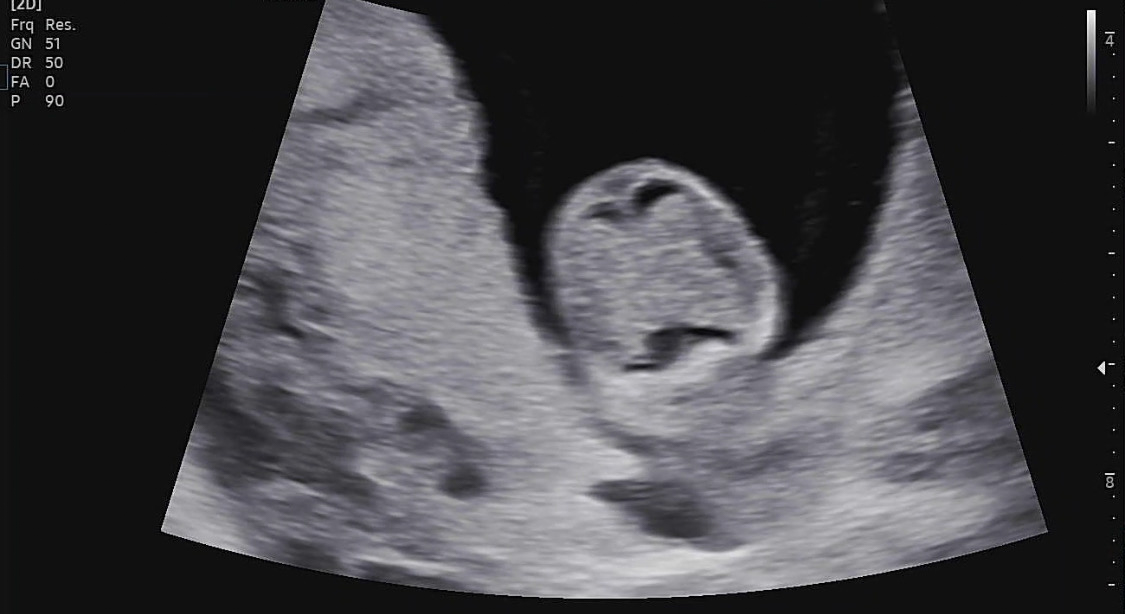

11주 5일

1차 기형아 검사를 받으러 갔다.

목투명대 검사

첫 검사는 정밀 초음파 검사실에서 이루어지는 목투명대 검사였다.

목투명대 길이 정상범위는 3mm 미만인데 1.05mm가 나왔다.

그리고 주수에 맞게 잘 크고 있었다.

비어있던 머리 공간도 어느새 나비가 자리잡고 있었다.

입체 초음파도 찍어주셨다.